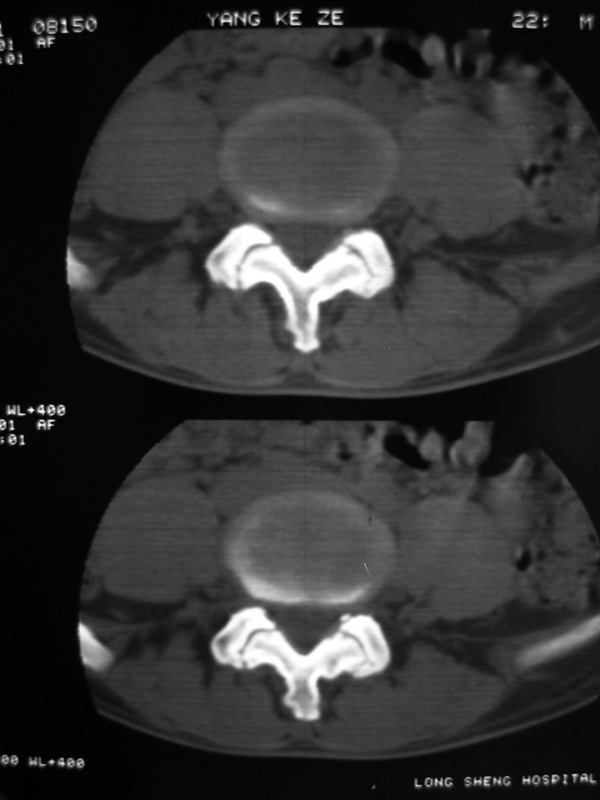

以下是引用w_jianhua在2007-3-8 11:14:00的发言:[br]椎小关节及右侧骶髂关节关节面毛糙,间隙不规则狭窄,骨皮质增生硬化,支持强直性脊柱炎,并椎间盘膨出

以下是引用fumaogui在2007-3-8 8:40:00的发言:[br]腰椎椎间关节增生硬化,关节间隙变窄,右侧骶髂关节间隙变窄,关节面硬化[br]考虑强直性脊柱炎.建议结合化验查:c--反应蛋白和类风湿因子.